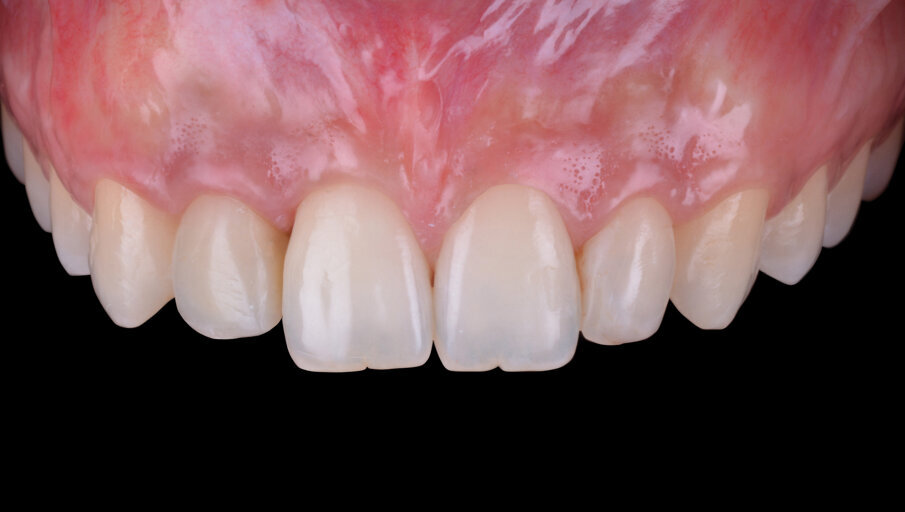

L’elemento dentario 1.2 riabilitato per mezzo di una corona avvitata su impianto dimostra una corretta e piacevole integrazione estetico-funzionale (Figg. 16, 17). I tessuti molli perimplantari sono caratterizzati da un corretto trofismo cervicale e un buon mimetismo radicolare; il fenotipo gengivale spesso ha agevolato il raggiungimento di un gradevole equilibrio estetico tra corona e tessuti molli e garantisce un sigillo transmucoso in grado di proteggere l’interfaccia abutmentimpianto e assicurare la stabilità della riabilitazione nel lungo periodo.

Risultati

Il caso clinico appena discusso mostra come, quando presenti le rispettive indicazioni, sia possibile riabilitare efficacemente quadri agenesici dell’incisivo laterale superiore con eccellente predicibilità del risultato e, nel rispetto dei protocolli chirurgico-protesici descritti, ottenere un successo terapeutico dal punto di vista estetico e funzionale. È chiaro come le tecniche di aumento dei tessuti molli e dei tessuti duri siano imprescindibili per traguardare un’integrazione estetica soddisfacente. A tal proposito la scelta del piano di trattamento aderente alle indicazioni, il protocollo chirurgico seguito step by step e l’utilizzo di biomateriali performanti hanno consentito lo svolgimento di una terapia ben sopportata e con un risultato ben accettato dalla giovane paziente. La letteratura ha ampiamente dimostrato come aumenti volumetrici dei tessuti duri e molli siano seguiti da una fisiologica contrazione dimensionale10-13, motivo per il quale, come si evince anche nel caso clinico presentato, è preferibile attuare un’ipercorrezione del difetto sovradimensionando gli innesti ossei durante le fasi chirurgiche di GBR14, 15.